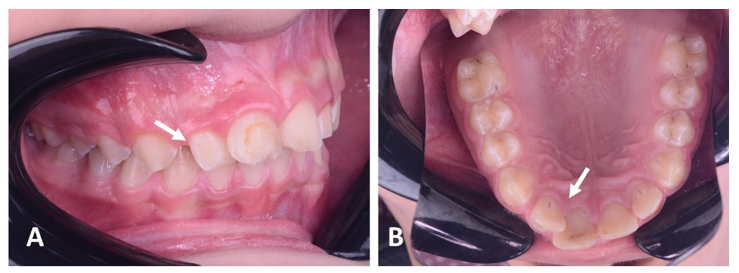

The patient did not report any painful symptoms during the 3-month rest treatment or at other follow-up visits. The case was clinically asymptomatic as all signs and symptoms had disappeared completely, and the gingiva appeared normal on follow‐up recall (Figure 3). Periapical radiographs show signs of healing of the periapical lesion, increasing radiopacity, and decreasing root divergence through follow‐up recall at 6, 12, and 18 months (Figure 4).

Figure 4 Periapical radiographs show increasing radiopacity and a decrease in root divergence through follow-ups at 6 (A), 12 (B), and 18 (C) months.